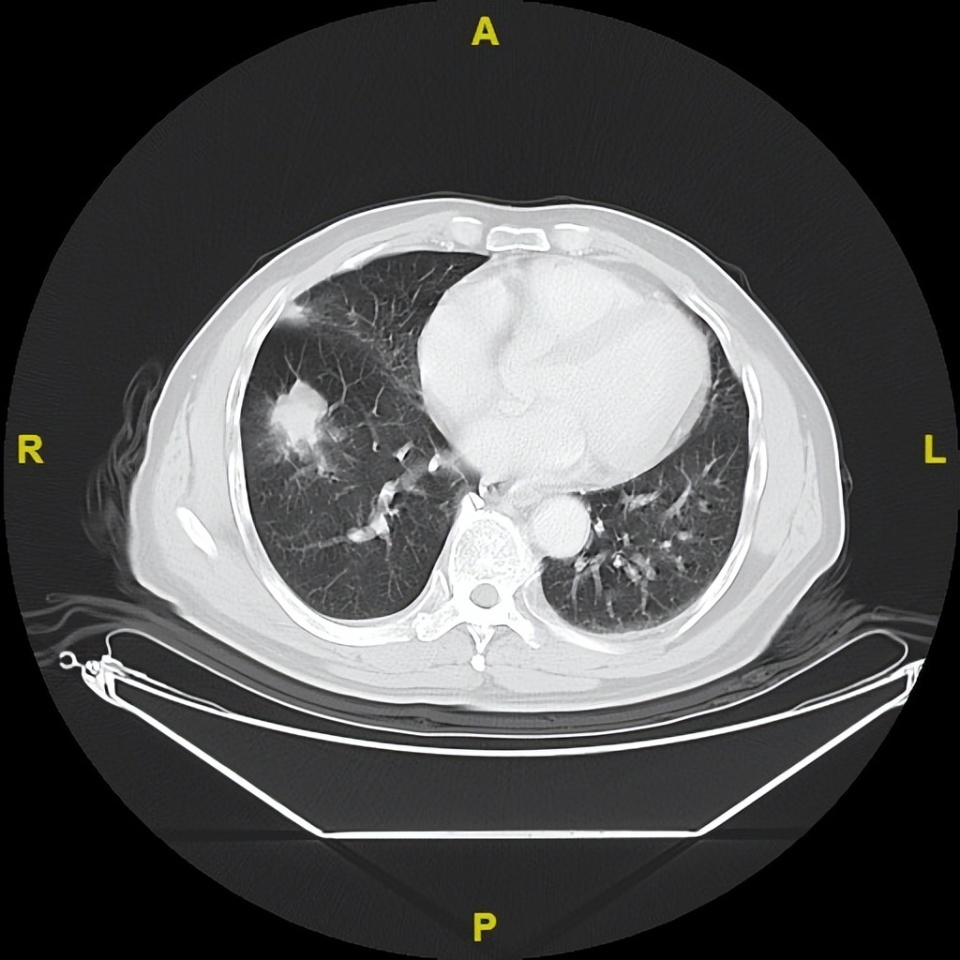

治疗第9周(C3)肿评:独立中心影像评估为疾病稳定(SD)。

治疗第15周(C5)起:连续 31 个周期经独立中心影像评估均为部分缓解(PR)。

治疗第108周(C36)起:序贯呋喹替尼5mg单药治疗,持续维持 PR,截至目前PFS 已达 38 个月,仍在持续获益。

△治疗后不同随访时间的胸部及髋关节CT病灶变化